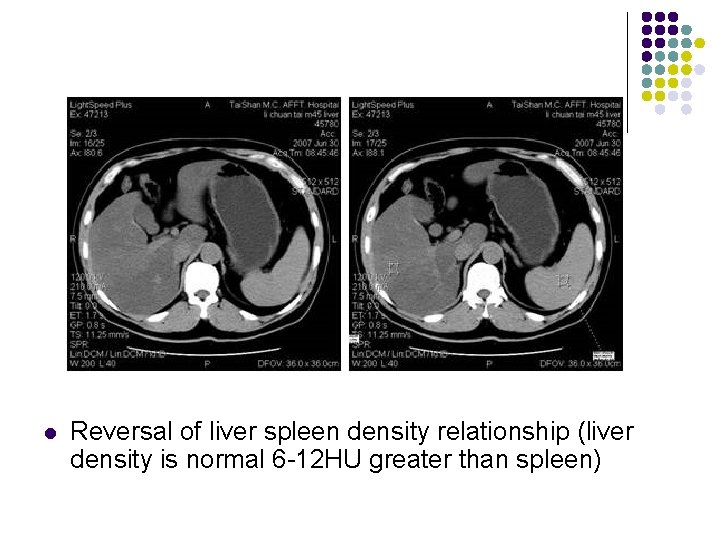

Diffuse Fatty Infiltration—CT l l l Areas of lower attenuation than normal portal vein/IVC density Reversal of liver spleen density relationship (liver density is normal 612 HU greater than spleen) Hyperdense intrahepatic vessels

l Reversal of liver spleen density relationship (liver density is normal 6 -12 HU greater than spleen)